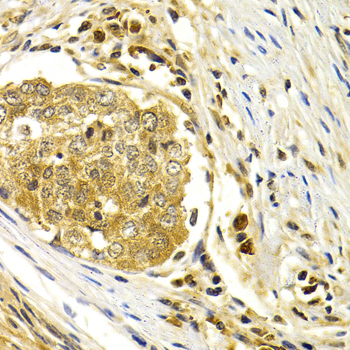

Immunohistochemistry of paraffin-embedded human stomach cancer using CDK7 antibody at dilution of 1:200 (400x lens).